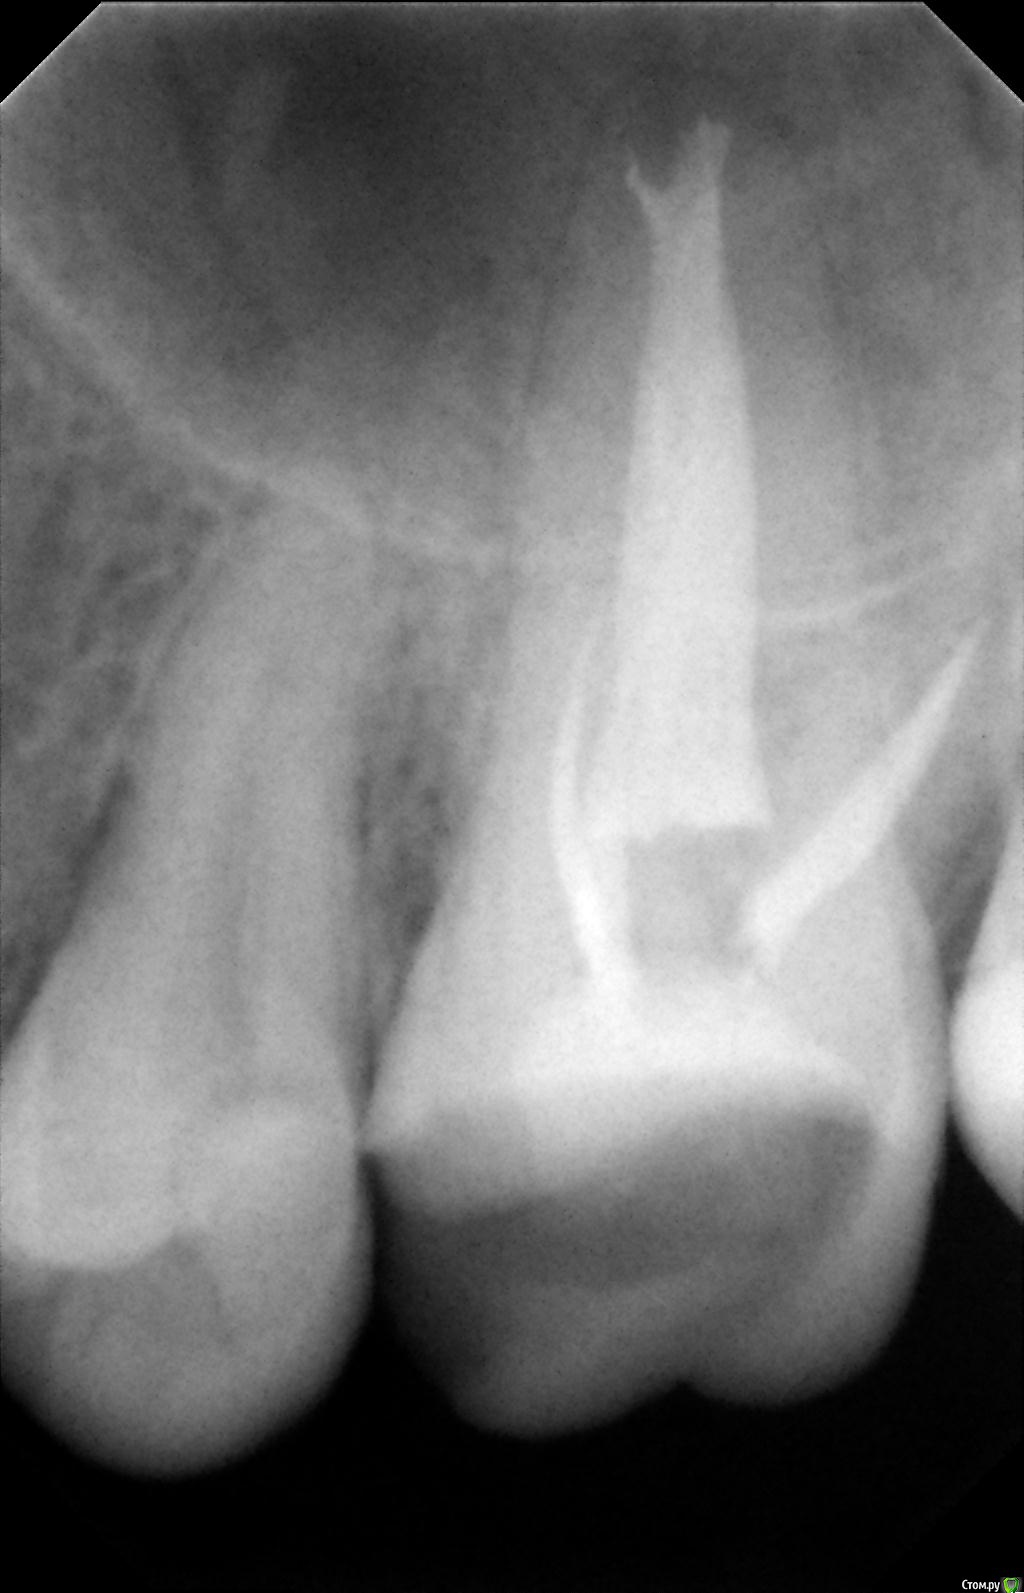

К сообщению прикреплены фотографии процесса лечения 26-го зуба.

После пломбировки каналов, я решил пойти ставить коронку в другую клинику, но там мне сказали, что не дают гарантию на этот зуб, поскольку каналы не долечены, и что я могу обратиться по гарантии в первую клинику. Но в первой клинике мне сказали, что все долечено. Хочу узнать мнение специалистов по этому поводу. Должен ли канал очищаться и пломбироваться до самой границы корня? Видно ли, что зуб не долечен по этим снимкам?

Так же в первой клинике в процессе лечения мне говорили, что у меня в зубе 5 каналов. Из-за этого цена лечения должна была быть еще дороже, но сказали, что мне оказали благосклонность и вылечили пятый канал бесплатно. В другой клинике мне сказали, что информация про 5-й канал - это ложь.